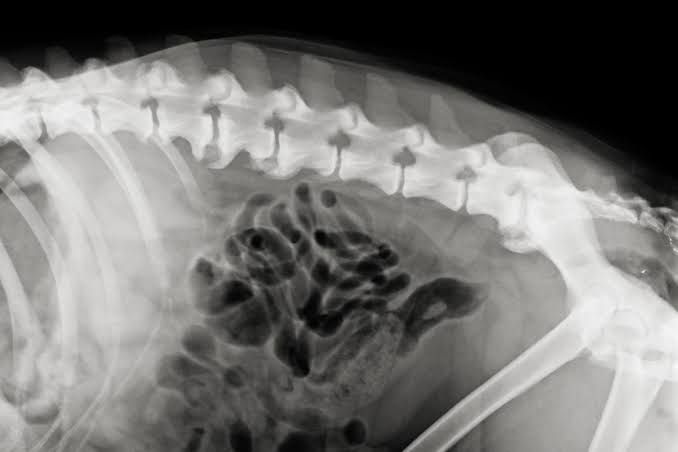

- X-Rays (Radiographs): X-rays are the most common diagnostic tool for identifying spondylosis. Radiographs can reveal the presence of osteophytes and other signs of spinal degeneration. The vet may take multiple X-ray views to examine different angles of the spine.

- MRI or CT Scan: In some cases, an MRI or CT scan may be performed to get a more detailed view of the spine, particularly if the condition is causing nerve compression or if additional spinal issues are suspected.